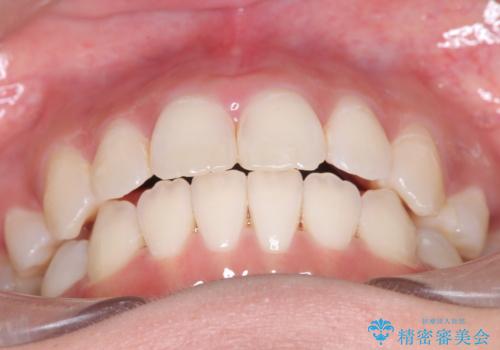

【インビザライン】シザーズバイト、抜歯矯正

- オープンバイトを主訴に来院された患者様です。

抜歯を行うことで、インビザラインを用いて前歯を下げることができ、同時にオープンバイトを改善することができました。

今回はインビザラインのみで治療を終了することができました。